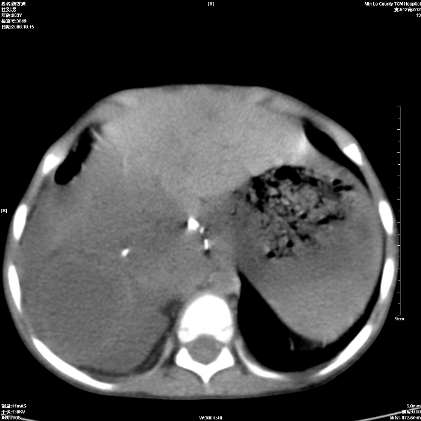

标题: PED1609:男性,3岁。彩超示肝Ca. [打印本页]

标题: PED1609:男性,3岁。彩超示肝Ca.

3岁;肝低密度灶;有钙化;有转移灶;考虑肝母细胞瘤;查afp

考虑:1、右侧后下纵隔畸胎瘤。

2、肝脏多发血管内皮细胞瘤。

建议:增强确诊。